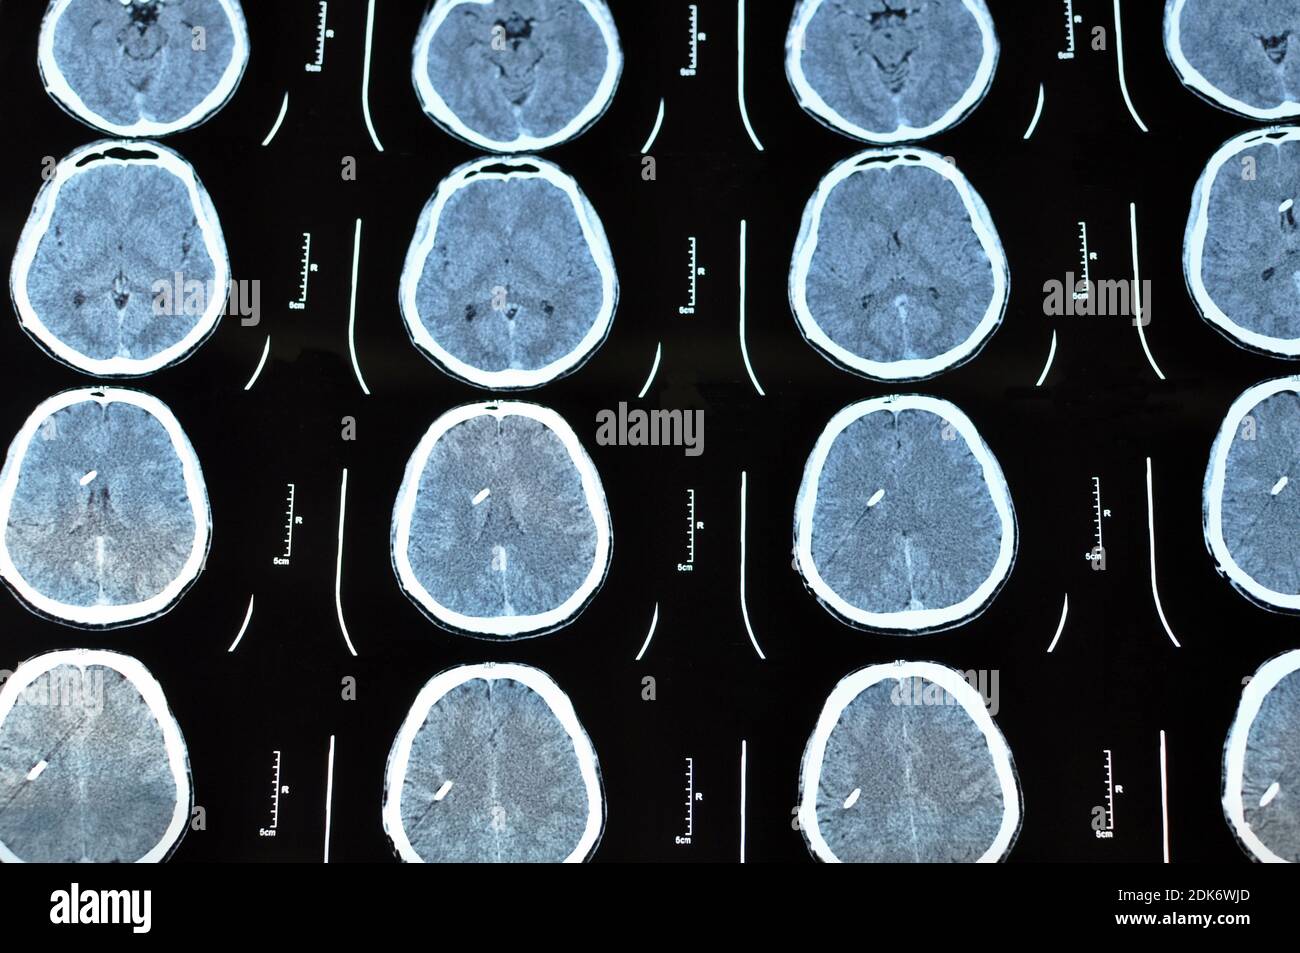

Acquisition d'images tomographiques du cerveau. Film CT d'un crâne et d'un cerveau humains avec shunt intracrânien. Antécédents de neurologie. Médecine, science. Banque D'Imageshttps://www.alamyimages.fr/image-license-details/?v=1https://www.alamyimages.fr/acquisition-d-images-tomographiques-du-cerveau-film-ct-d-un-crane-et-d-un-cerveau-humains-avec-shunt-intracranien-antecedents-de-neurologie-medecine-science-image390458389.html

Acquisition d'images tomographiques du cerveau. Film CT d'un crâne et d'un cerveau humains avec shunt intracrânien. Antécédents de neurologie. Médecine, science. Banque D'Imageshttps://www.alamyimages.fr/image-license-details/?v=1https://www.alamyimages.fr/acquisition-d-images-tomographiques-du-cerveau-film-ct-d-un-crane-et-d-un-cerveau-humains-avec-shunt-intracranien-antecedents-de-neurologie-medecine-science-image390458389.htmlRF2DK6WJD–Acquisition d'images tomographiques du cerveau. Film CT d'un crâne et d'un cerveau humains avec shunt intracrânien. Antécédents de neurologie. Médecine, science.